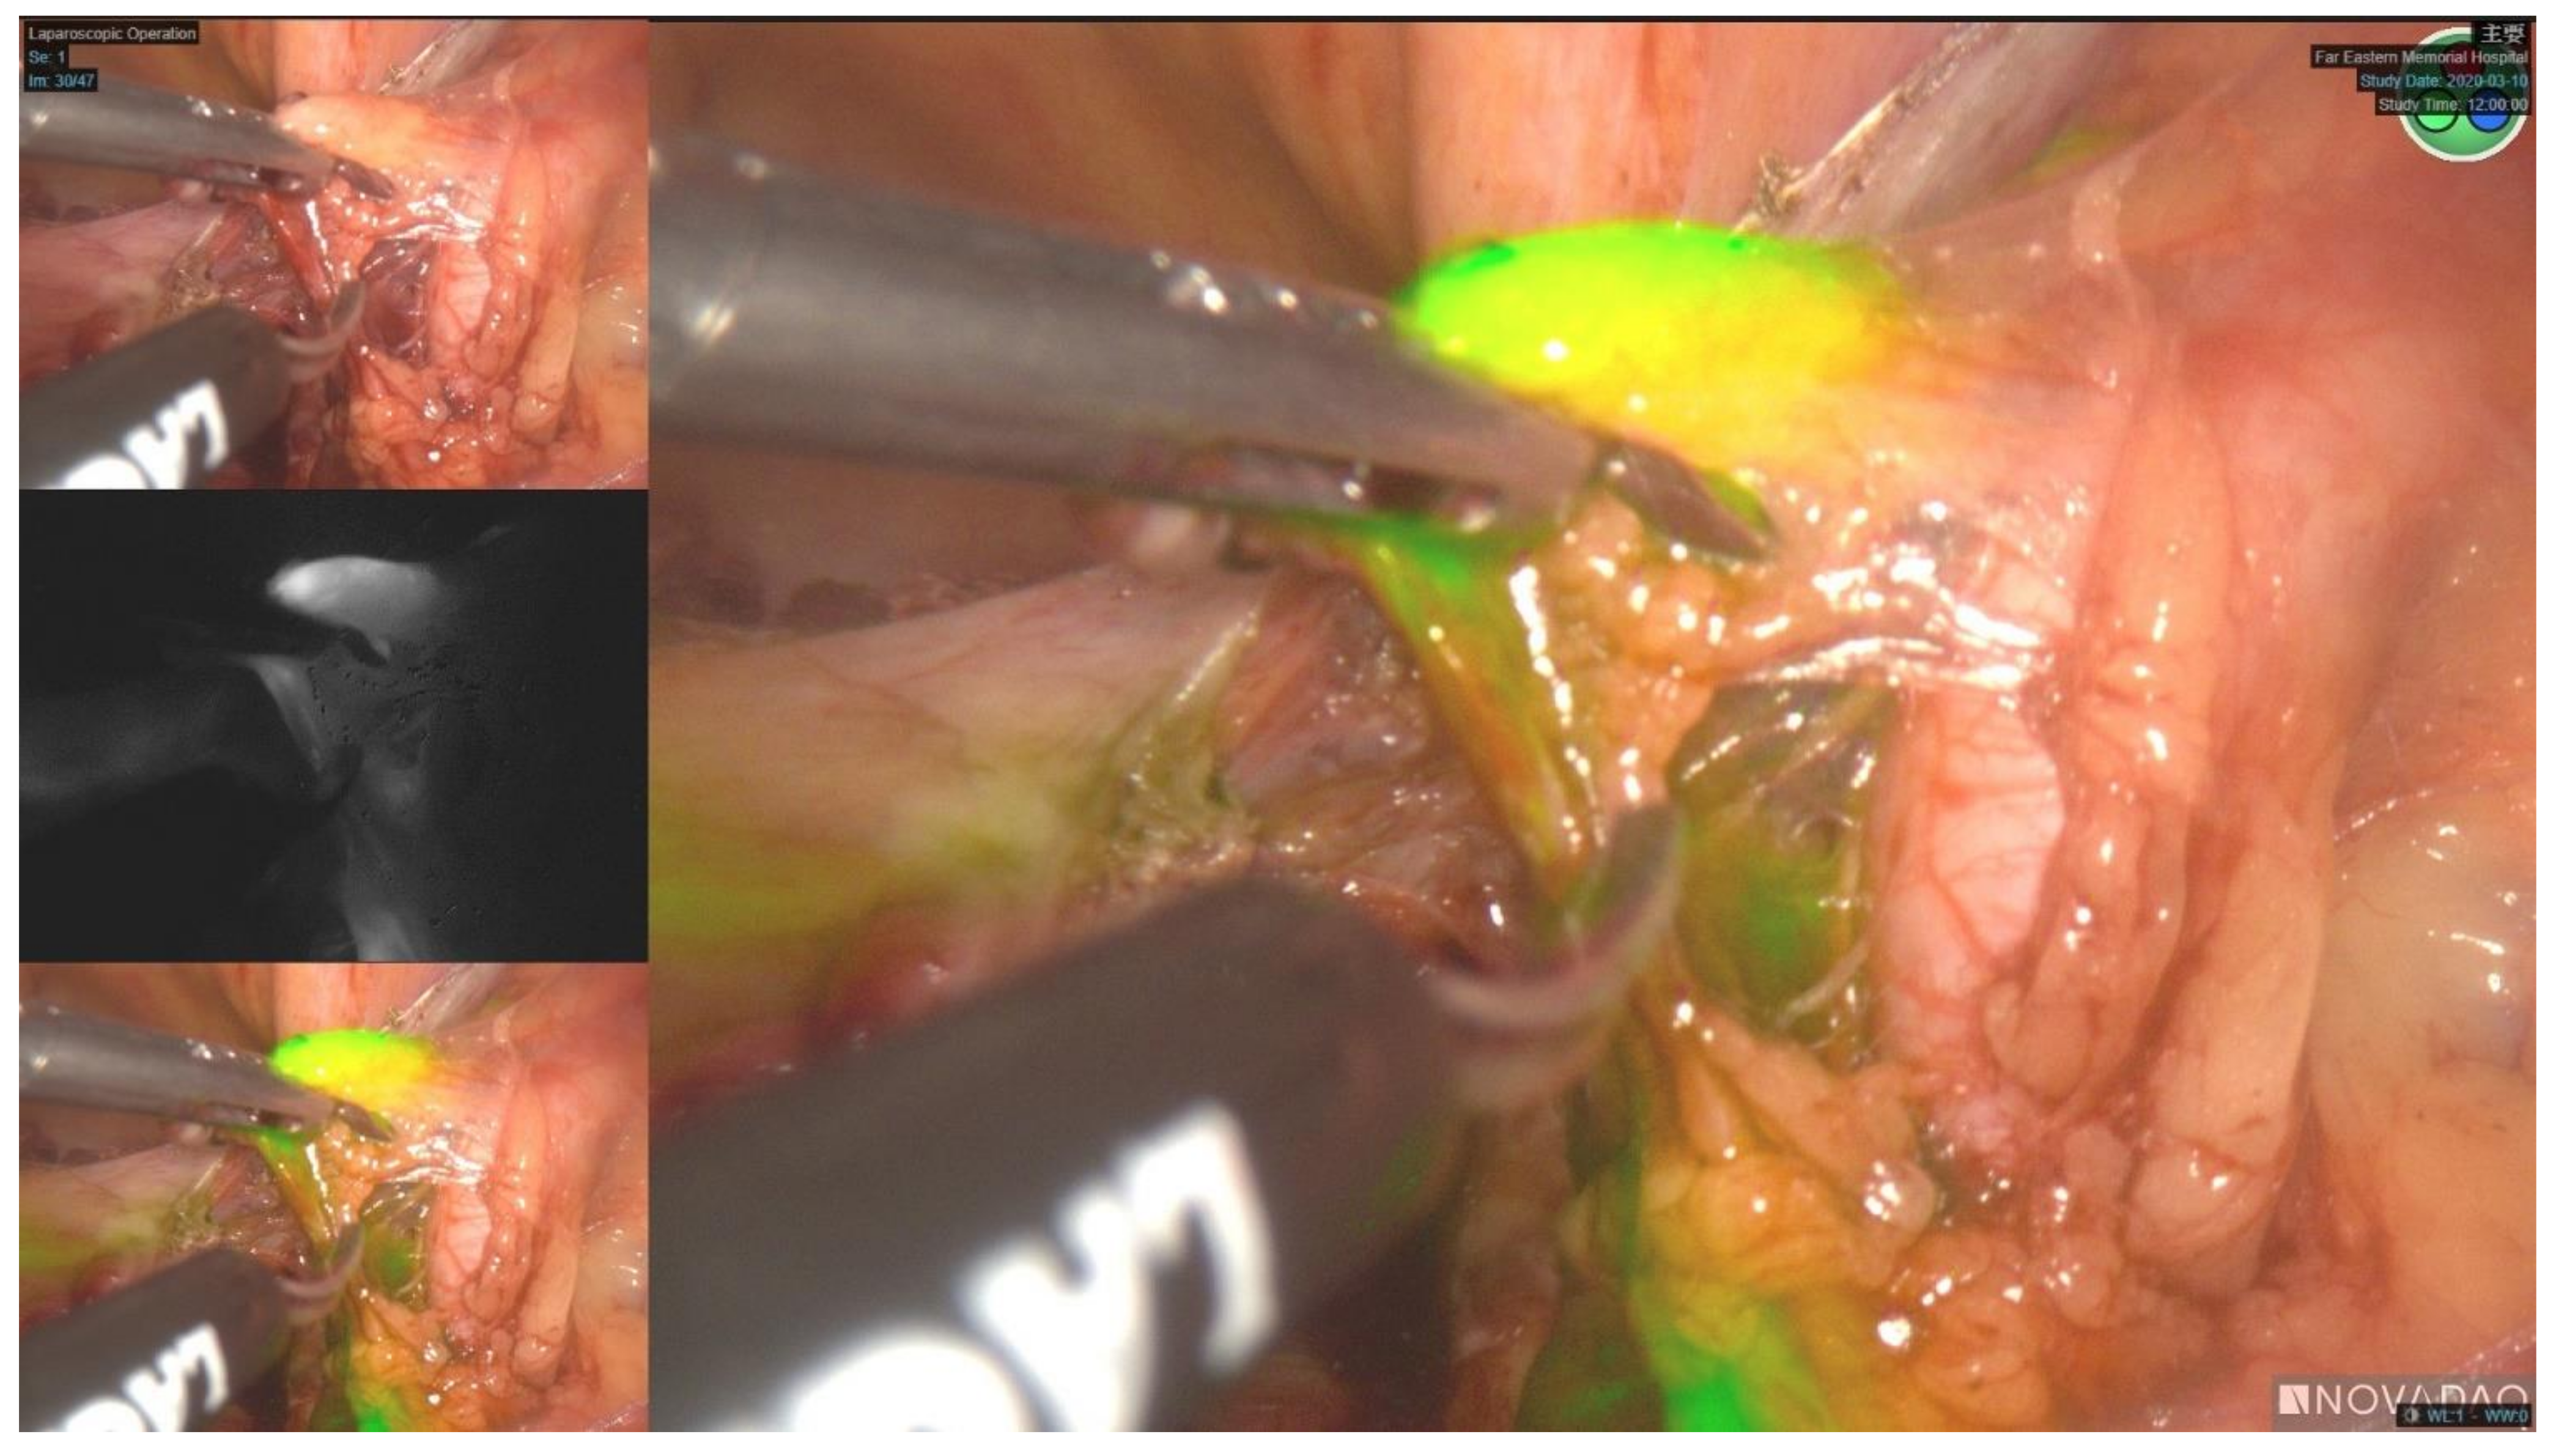

2. Materials and Methods